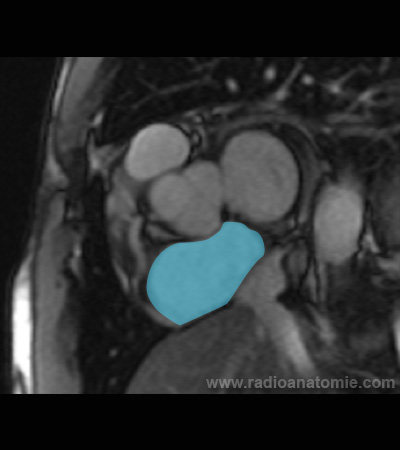

Radioanatomie et plans de coupe en IRM cardiaque

Oreillette droite